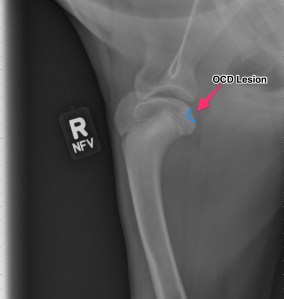

Radiographs (X-rays)

Above are x-rays of a left and right shoulder affected with OCD lesions. These are on the same patient. The images labeled with the left (L) marker has a flattened region noted by the arrow which is characteristic of OCD. The image on the right has the area highlighted in blue. While the lesion doesn’t look big, it can definitely cause a lot of pain and discomfort.